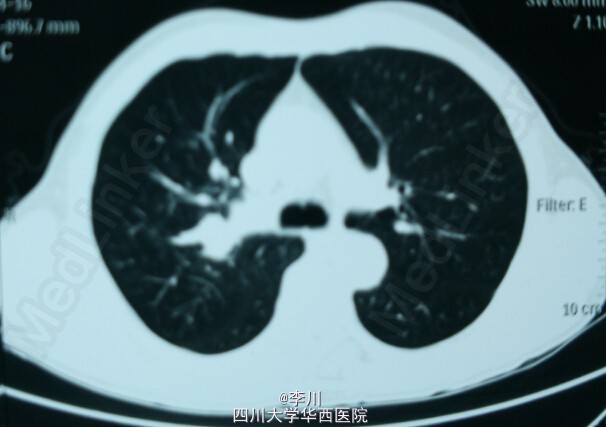

患者,男,63岁,因“咯血10天,发现右肺上叶鳞癌5天”入院。10天前患者无明显诱因出现咳嗽,咯血,为鲜红色,量约100ml,于当地医院行CT检查提示:右肺上叶支气管内充盈缺损,增强扫描不均匀强化。

心肺腹查体无特殊异常。纤支镜提示:右上叶开口见菜花样新生物将管腔完全阻塞,表面血管丰富,活检易出血,边界距隆突约1cm,病检提示:查见癌细胞,倾向于鳞癌。